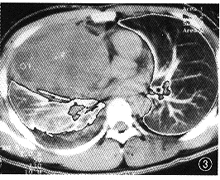

例2 患者男,22岁。因胸闷气促,右胸痛,咳嗽2月于1999年7月2日入院。入院体检:一般情况差,抬入病房,呼吸急促,神志清,唇无紫绀,颈静脉无怒张,心率115次/min,律齐,右侧呼吸运动较左侧降低,右肺语颤较左侧减弱,叩诊呈浊音,呼吸音明显减轻,左肺呼吸音粗,未闻及音。腹部未见异常,双下肢无水肿。血白细胞8.4×109/L,中性0.66,淋巴0.34,血红蛋白92 g/L,肝肾功能、电解质均正常。多次浓缩痰找抗酸杆菌及痰脱落细胞检查均阴性。心电图示窦性心动过速。动脉血气分析在正常范围。B超示右胸腔中等量积液。腹、脑CT均未见异常。胸部X线示右侧第一前肋以下至横膈有大片致密影,右侧肋膈角、横膈面消失,左侧未见病灶(图2)。胸部CT示右前纵隔见巨大类椭圆形软组织影,约13 cm×12 cm×16 cm,边缘毛糙分叶,僵硬感,其内密度不均,CT值为6.5 Hu~30.3 Hu,不规则增强,无钙化灶。右前胸壁肋间隙扩大,心影及大血管向左后推移,右上叶前段、中叶支气管受压,变窄,右侧胸腔见中等量积液,局部包裹伴结节,右下肺压缩,不张,左肺无病灶(图3)。于1999年7月9日行开胸手术。术中见肿瘤上达锁骨水平,下至横膈,上下径30 cm,左右径约5 cm,前后径25 cm,侵犯右侧心包范围达8 cm×8 cm。肿瘤呈分叶状,暗褐色,有弹性,并有局部液化,侵犯右下叶及中叶,故行右全肺加肿瘤切除术。病理标本见右全肺胸膜广泛粘连,肿块与下叶紧密相连,肿块约16 cm×9 cm×8 cm,红褐色,右全肺受压,萎缩。病理证实为右前纵隔恶性卵黄囊瘤,心包受侵。术后恢复良好,于7月29日出院。